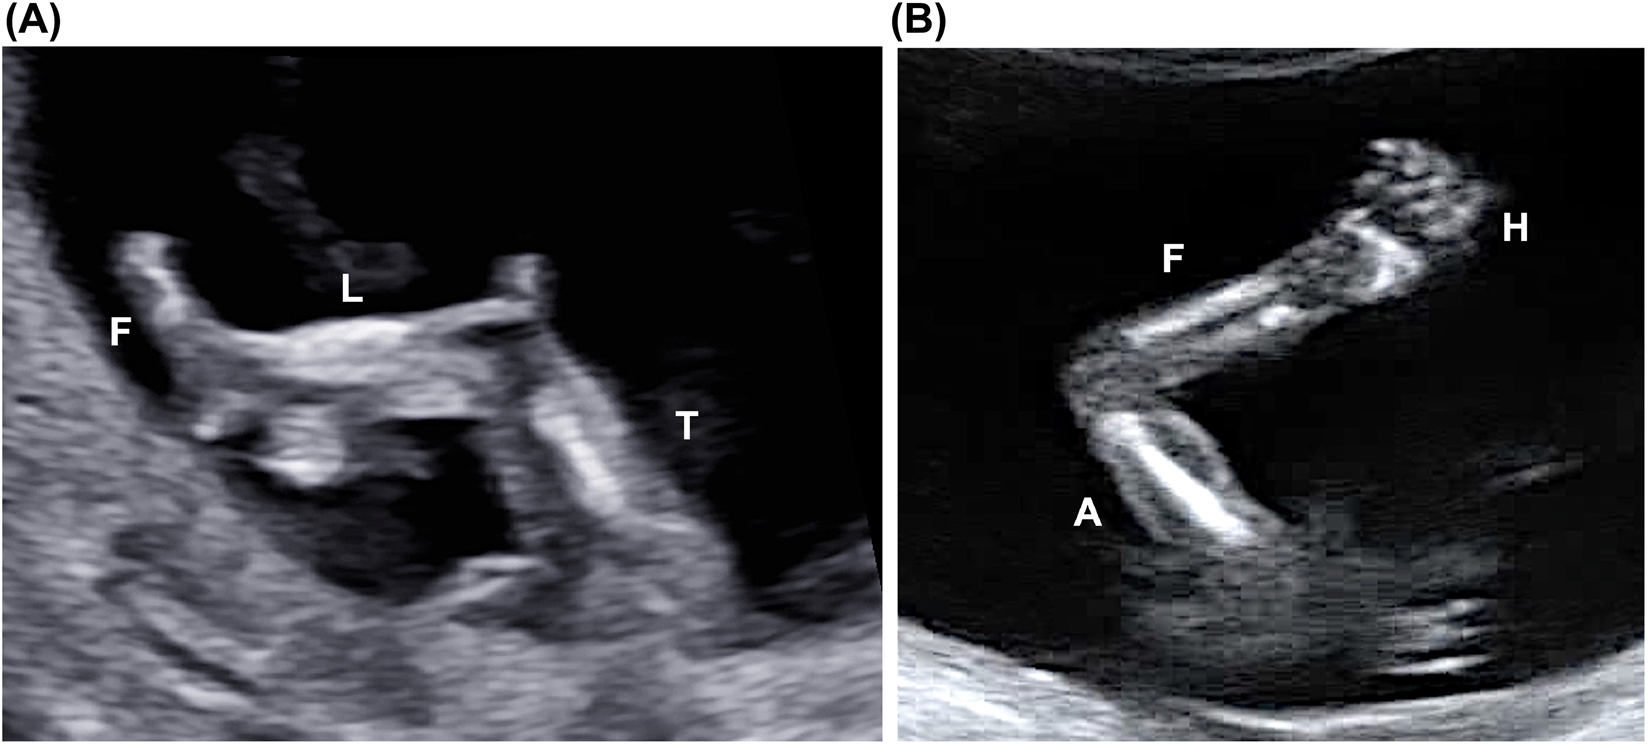

Limbs

Under normal conditions, the three segments of each limb could be visualized: thigh, leg, and foot in both lower limbs; arm, forearm, and hand in both upper limbs (Figure 13). Long bones should look straight, with regular proportions. The position of the three segments, in particular hands and feet, should also be evaluated, and an excessive rotation or bending should be excluded. In favorable conditions, dedicated views of the open hands and the foot soles could show normal fingers and toes. Spontaneous active fetal movements should also be noted.

Lower (A) and upper (B) limbs. In (A) the tight (T), the leg (L) and the foot (F) are visible. In (B) it is possible to visualize the arm (A), the forearm (F) and the hand (H).

The presence of the three segments of the limbs, including hands and feet, should be routinely assessed.

Active fetal movements should also be visualized and reported routinely.